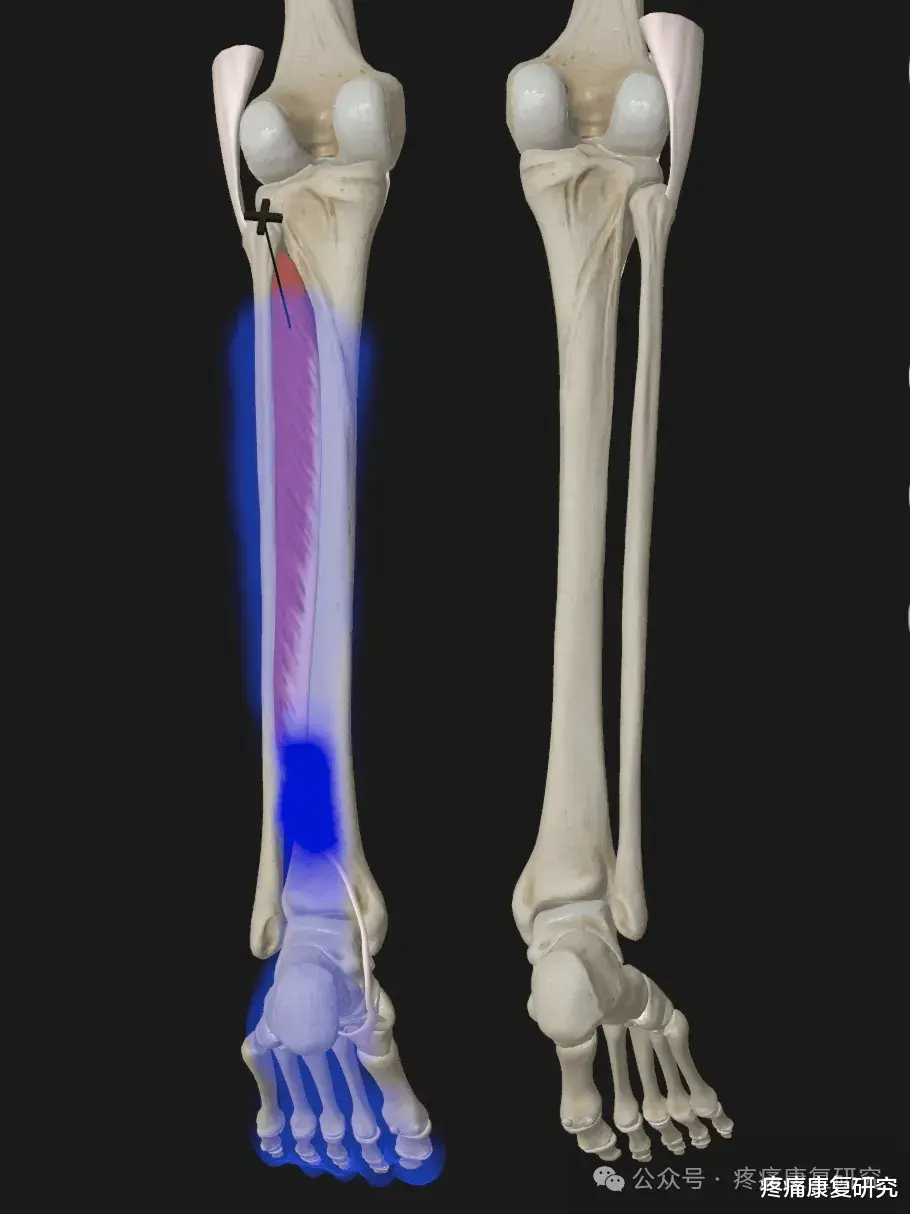

二、胫骨后肌失能后的典型表现

1.足弓塌陷:

内侧纵弓变平,足底负重面扩大,出现扁平足体征(最直观的外在表现);

2.足部力线异常:

行走时足部过度外翻、外旋,引发踝部内侧疼痛(肌腱止点或走行区压痛,典型疼痛部位);